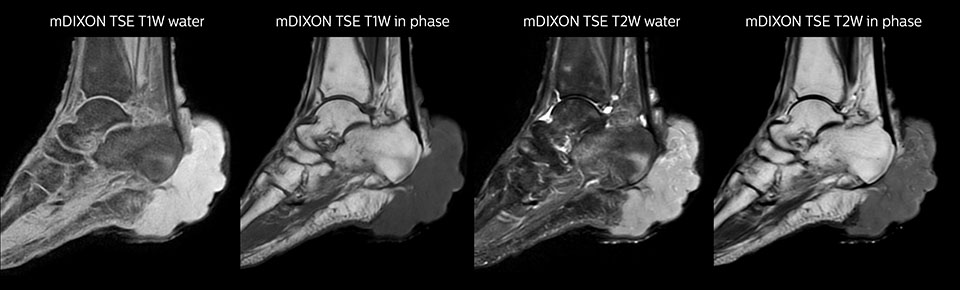

At Seirei Mikatahara General Hospital in Shizuoka Prefecture, Japan, Prodiva 1.5T is making impact, too. Radiologist Dr. Takahashi and his colleagues in the large radiology department operate three MRI scanners, including an Ingenia 3.0T, to serve a population that includes many elderly people. When the time came to replace an older MRI system, they chose Prodiva 1.5T – and the clinical capabilities and workflow advantages of their newest scanner have had a real impact. Dr. Takahashi says: “For a 1.5T, Prodiva delivers excellent quality, which really exceeded my expectations. We now even perform some exams on Prodiva that we would previously only do on a 3T.” High SNR, motion-free images and excellent homogeneity of the magnetic field help the team achieve excellent results. “I really appreciate the quality of fat saturation with mDIXON XD, especially in the neck area and joints of extremities, which were often problematic for us,” says Dr. Takahashi. “Since introducing the Prodiva, we have had to perform fewer rescans due to the high SNR, motion-free images, and excellent homogeneity of magnetic field.” Dr. Takahashi uses Prodiva 1.5T for a variety of examinations, including cardiac, vascular, abdominal and musculoskeletal. Furthermore, he also performs whole body imaging using T1, STIR, T2WI and diffusion sequences on the Prodiva system. “I’m impressed by the short patient preparation time and fast scan time,” he says. “Typically, diffusion imaging in body is quite challenging due to distortions. We get very good results in body diffusion with Prodiva.”

MRI examination on Prodiva 1.5T of a 72-year-old female with a malignant melanoma in the ankle. mDIXON TSE provides excellent fat suppression, without the distortion that is often seen at such extremities.